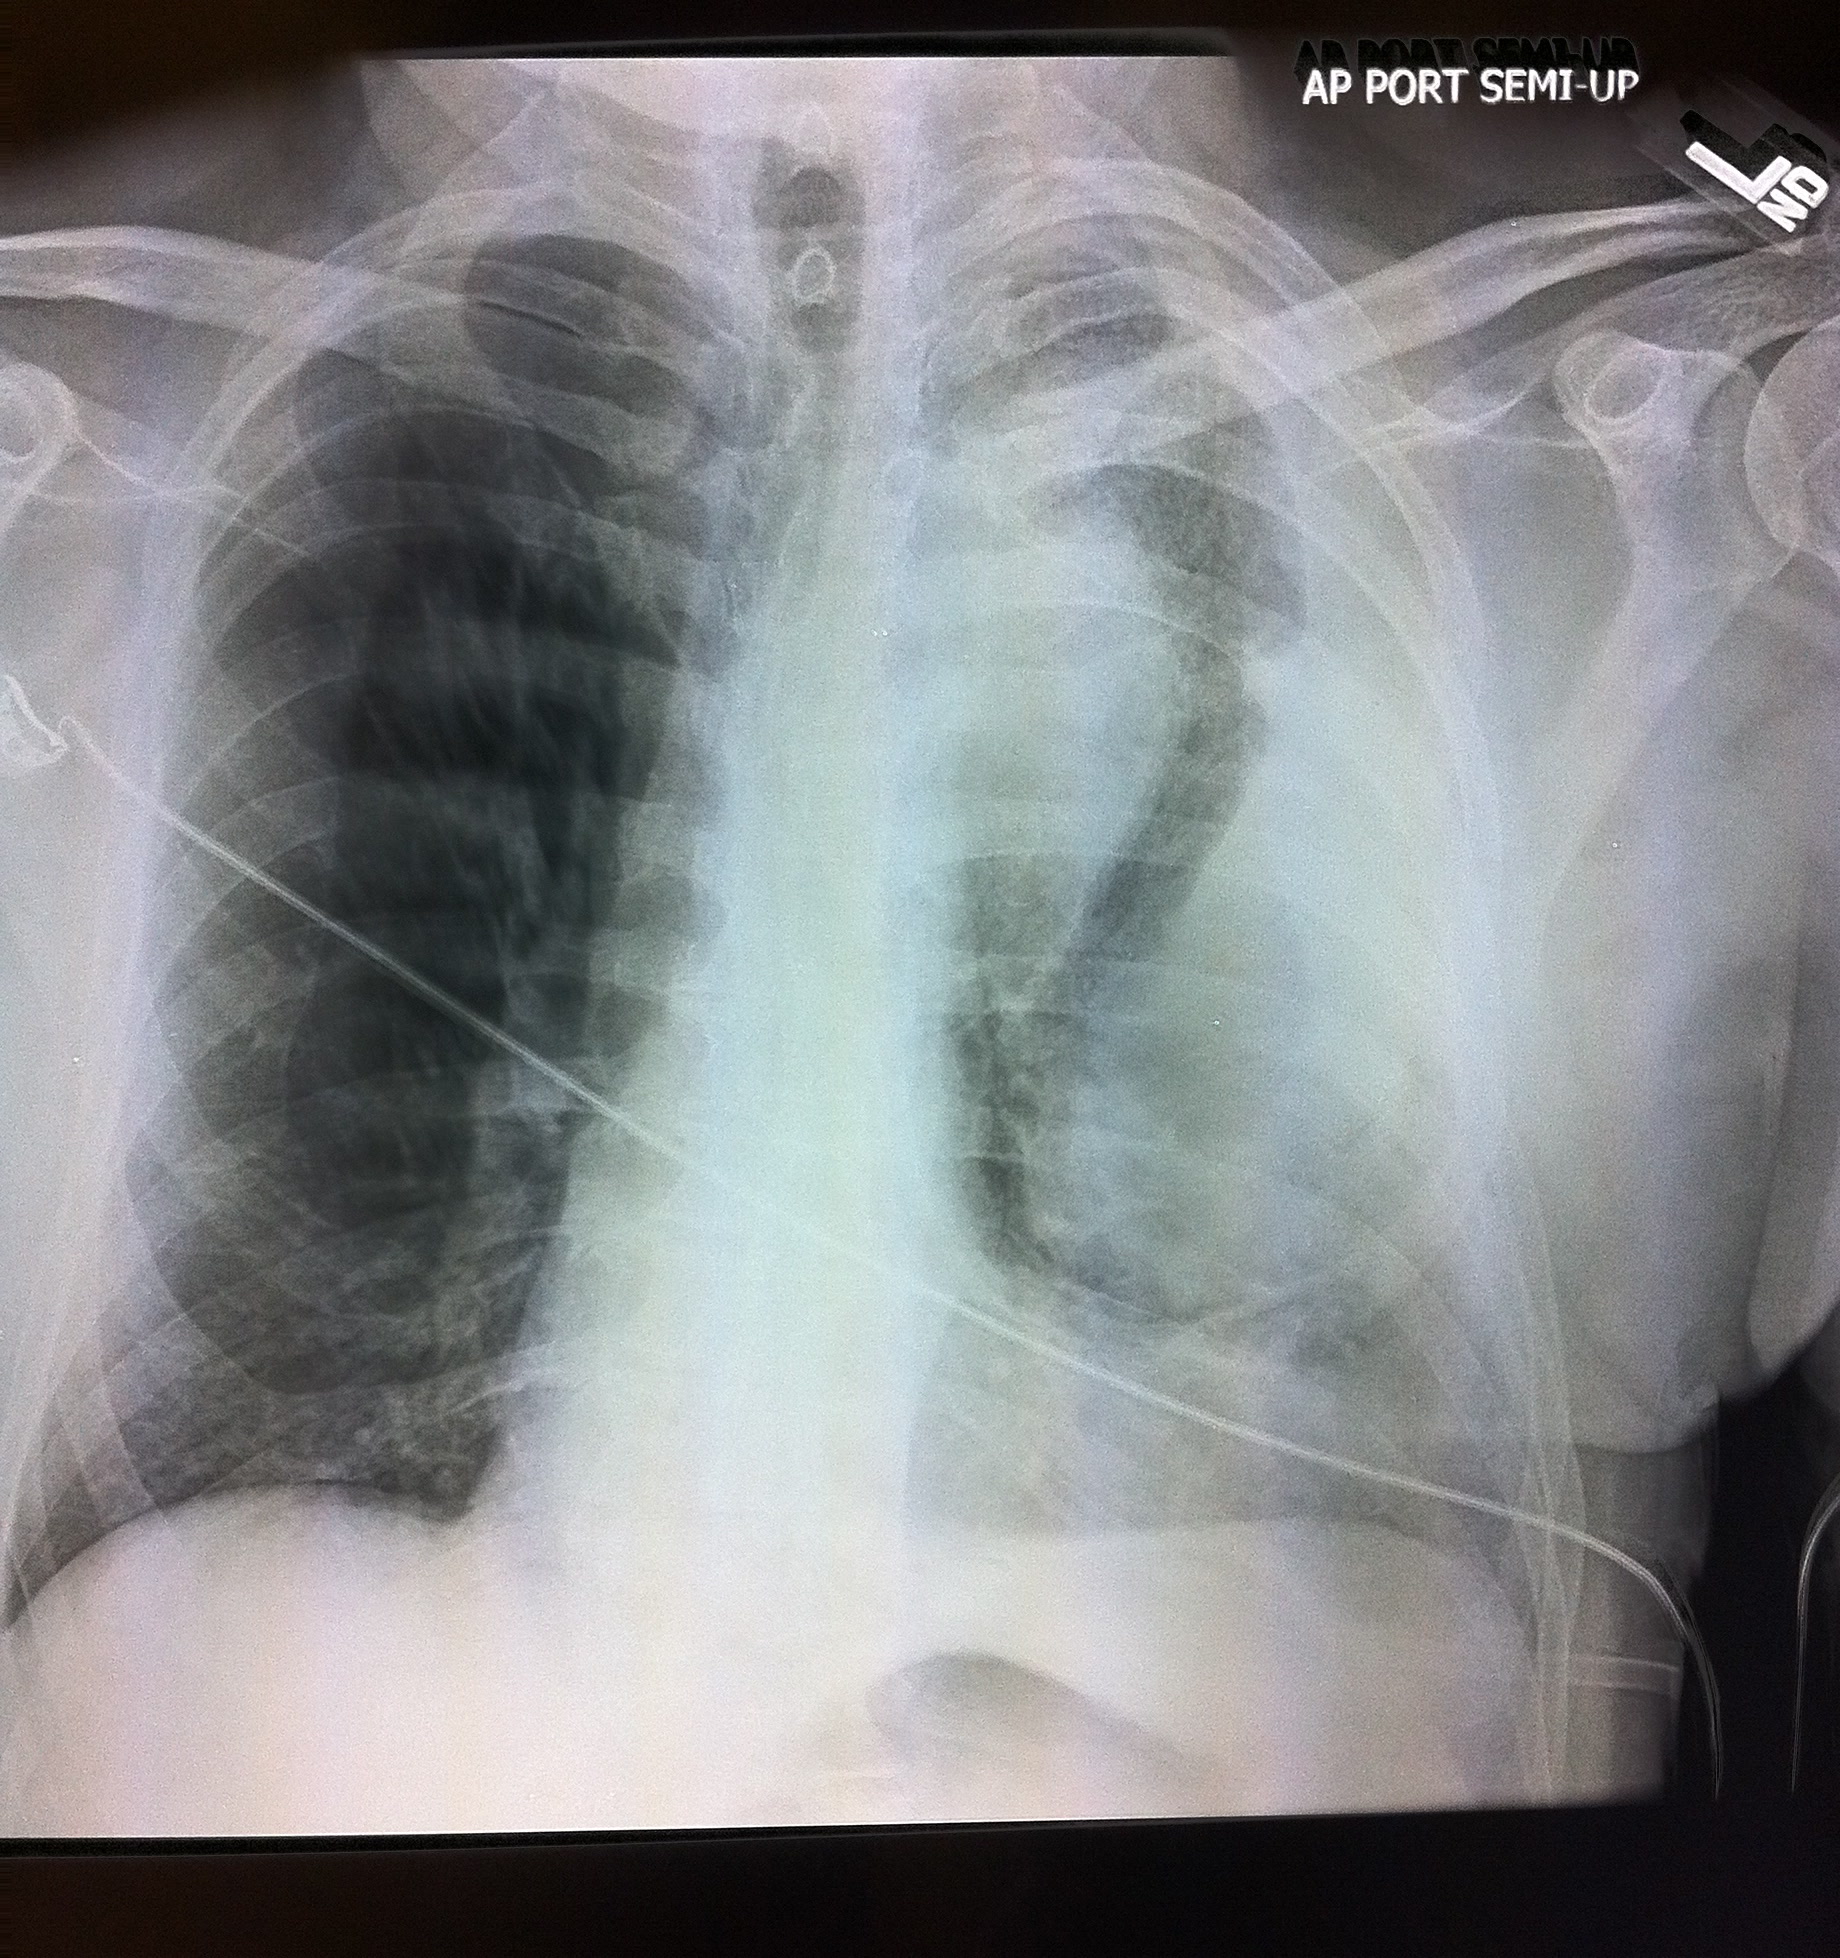

That left side had no lung sliding and a stratosphere sign on M Mode, that’s the first thing that Dr. Chough appreciated, but it was also unclear as to why it was so echogenic (gray) beneath the pleural line. He had no signs of tension pneumothorax on clinical exam, so instead of performing a needle thoracostomy and chest tube, she aborted the rest of the RUSH and ordered a stat Chest XR:

Given the above findings of a dilated aortic knob and correlating that to the small pericardial effusion, left sided pleural effusion, and clinical findings, she realized what she was seeing was a ruptured ascending thoracic aneurysm (with blood entering the pericardial space and the leaking blood collecting on the left side of his chest – as the aorta is situated on the left side and that’s where blood will go). His HR remained between 55-65 and his BP remained between 70s-100s with normal mentation. A stat CT angio of his chest was ordered and cardiothoracic surgery was called. As I dont usually provide CT images, this one was an interesting one and explained why Dr. Chough saw gray on the left anterior chest beneath the pleural line: